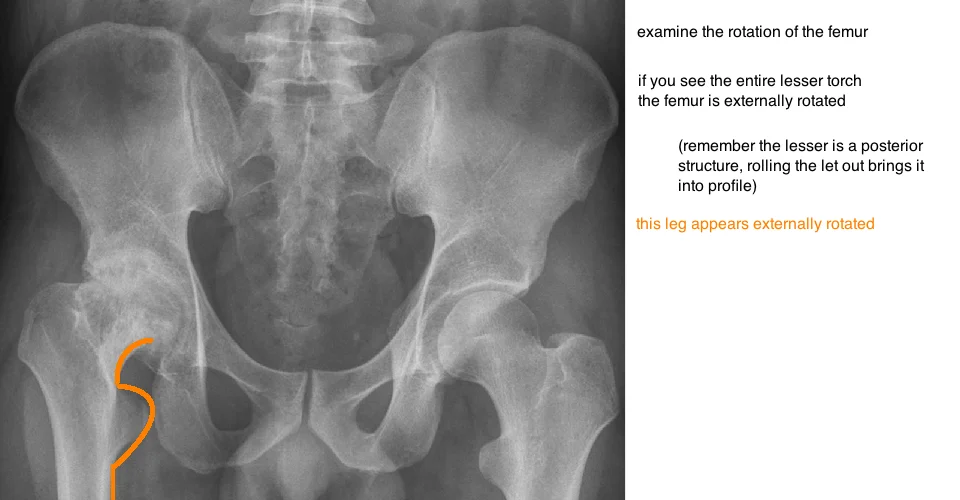

evaluating hip rotation on xray ap pelvis

femoral rotation on pelvis xray